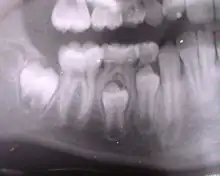

La denture humaine possèdent 32 dents permanentes. Les 8 incisives, les 4 canines et les 8 prémolaires remplace les 20 dents déciduales, les prémolaires remplaçant les 4 molaires déciduales.

Les 12 molaires permanentes poussent comme dent permanentes dés la première pousse.

La première dent définitive fait son éruption vers 5-6 ans : c'est la première molaire ("dent de 6 ans"). La dernière vers 12-13 ans ; c'est généralement une prémolaire sans compter les dents de sagesse inconstantes pouvant apparaître jusqu'à 25 ans.